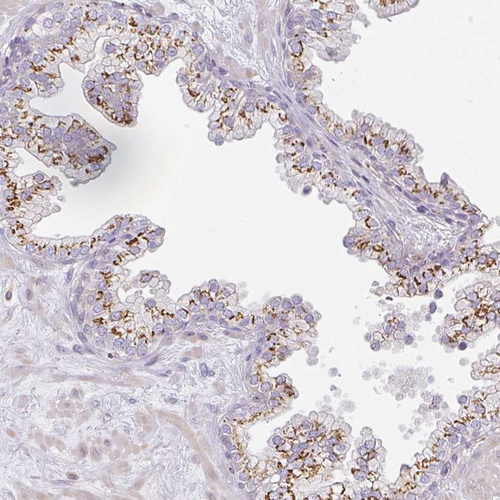

Immunohistochemical staining of human Prostate shows strong granular cytoplasmic positivity in glandular cells.